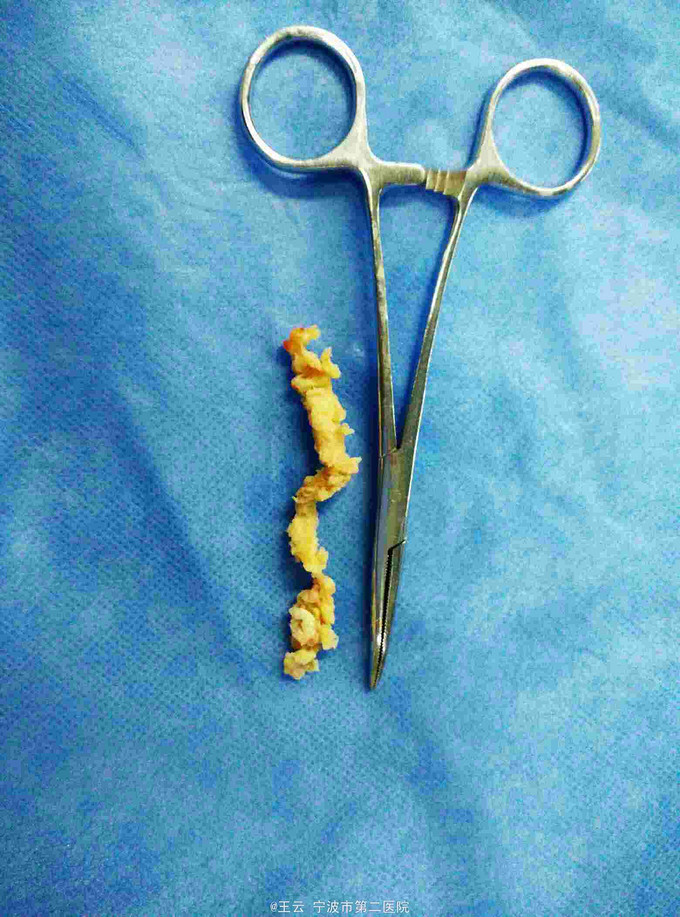

腰3/4椎间盘脱出向下高度游离

诊断:L3/4椎间盘脱出 治疗:经椎间孔入路椎间孔镜下髓核摘除,射频消融

术后症状立刻缓解,直腿抬高实验80度阴性。